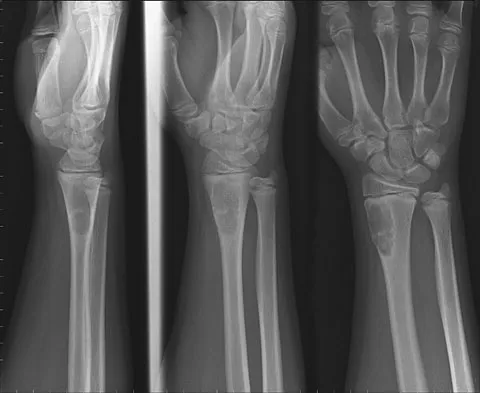

Figures 45a and 45b show the radiographs of a 14-year-old boy who sustained a distal radius fracture while playing hockey. After 1 year the patient is asymptomatic. Follow-up and comparison radiographs and an MRI scan are shown in Figures 45c and 45d. What is the next most appropriate step in management?

Explanation

The patient sustained a growth plate fracture of the distal radius and ulna. Although treated with closed reduction and casting, the follow-up radiographs demonstrate shortening of the radius in comparison to the ulna, and the MRI scan confirms thinning of the distal radius growth plate and bony bars consistent with a growth arrest. At this time, the discrepancy in length is too minor to consider lengthening of the radius; in addition, excision of a physeal bar with minimal growth potential is not likely to restore the gross discrepancy. Ulnar styloid fractures are rarely symptomatic and do not require treatment in the asymptomatic patient. Closure of the distal ulna growth plate will prevent further discrepancy between the radius and ulna. Vanheest A: Wrist deformities after fracture. Hand Clin 2006;22:113-120.